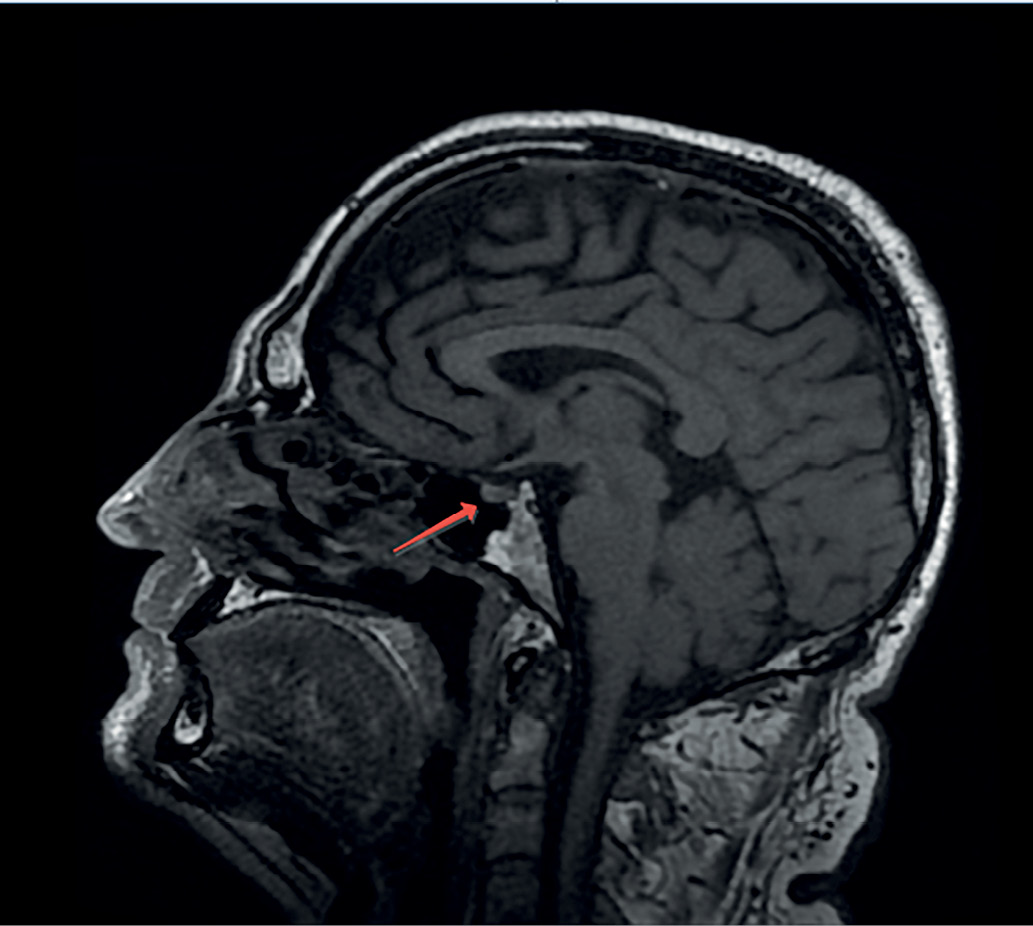

С целью визуализации хиазмально-селлярной области пациенту выполнена магнитно-резонансная томография (МРТ), которая не выявила опухолевых или воспалительных образований и аномалий развития головного мозга. Гипофиз имеет нормальные размеры: вертикальный — 5 мм, поперечный — 13 мм, переднезадний — 9,1 мм. Структура аденогипофиза однородная, воронка расположена по средней линии (рис. 1, 2). Отмечено отсутствие типичного сигнала от задней доли гипофиза,а проведение контрастного усиления не выявило каких-либо дополнительных изменений гипоталамо-гипофизарной области, в связи с чем диагноз идиопатического ЦНД у пациента был подтвержден.

Рисунок 1. МР-картина хиазмально-селлярной области пациента. Фронтальный срез.

Figure 1. MRI of the patient's chiasmal-sellar area. Front cut.

Рисунок 2. МР-картина хиазмально-селлярной области пациента. Сагиттальный срез.

Figure 2. MRI of the patient's chiasmal-sellar area. Sagittal section.

Важным параметром МРТ, высокоспецифичным для ЦНД, является снижение характерного свечения от нейрогипофиза на Т1-взвешенных изображениях. Гиперинтенсивность задней доли, наблюдаемая в норме, происходит от наличия секреторных гранул, богатых фосфолипидами, в которых содержится АДГ. При нарушении синтеза и секреции АДГ, а также в ситуациях его повышенных трат (например, декомпенсированный сахарный диабет) такой сигнал пропадает и обе доли имеют одинаковую интенсивность. Таким образом, отсутствие характерного сигнала от нейрогипофиза по данным МРТ головного мозга у представляемого нами пациента дополнительно свидетельствовало о наличии ЦНД.